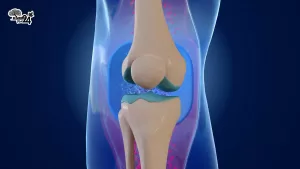

¿Por qué es tan importante el colágeno en las articulaciones?

El colágeno funciona como un amortiguador dentro de tus rodillas. Imagina que es como ese “relleno” que evita que los huesos choquen entre sí. Cuando el colágeno disminuye —ya sea por la edad, por una dieta deficiente o por desgaste físico— las articulaciones pierden elasticidad y aparecen el dolor y la inflamación.

Aquí es donde entran en juego estas dos verduras. Gracias a sus nutrientes, no solo ayudan a tu cuerpo a producir colágeno, sino que también mantienen en buen estado los tejidos ya existentes. Esto es clave si quieres mantenerte activo, hacer ejercicio sin molestias o simplemente moverte sin sentir dolor en las rodillas.